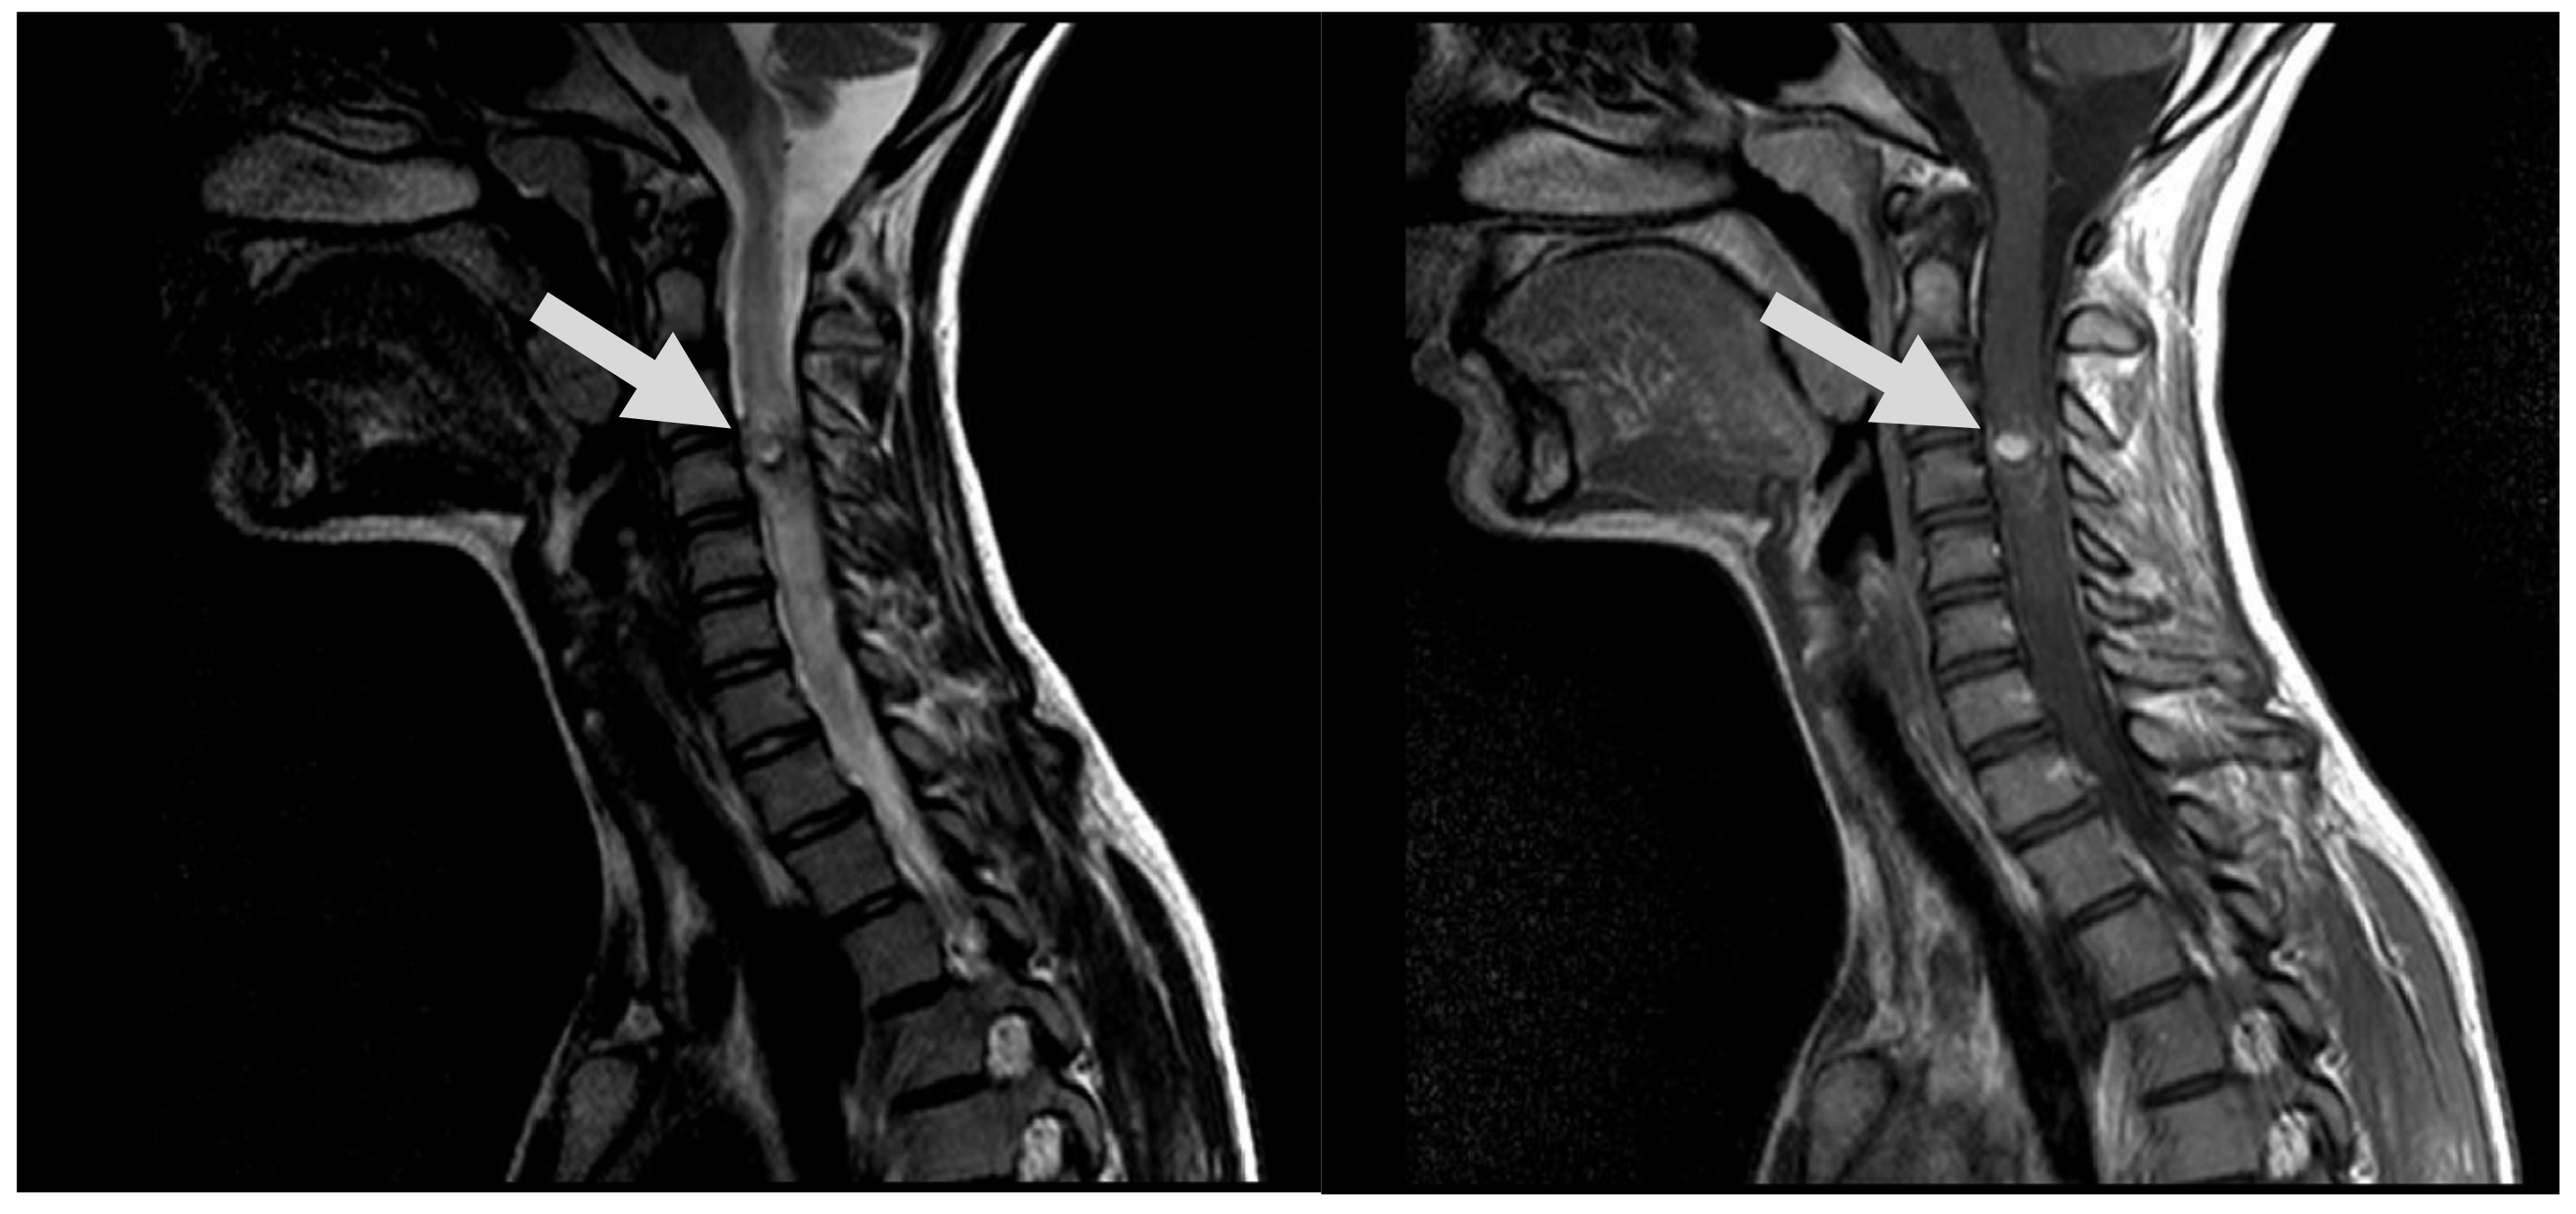

7.1. First Episode (2011)

7.2. Second Episode (2020)